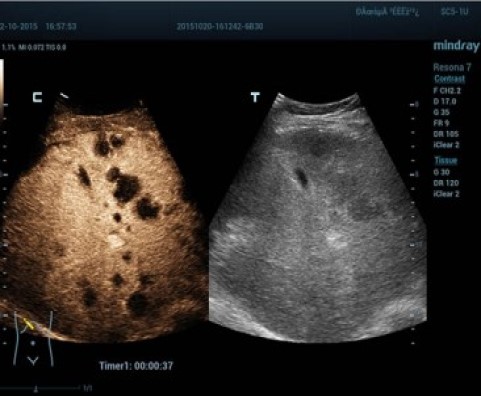

С момента основания компания Mindray непрерывно ищет новые способы повышения точности диагностики. Основанная на самой передовой технологии ZONE Sonography? новая платформа ZST+, выводит качество ультразвуковой визуализации системы Resona 7 на более высокий уровень за счет использования зонного сканирования и канальной обработки данных.

Обеспечивая качество изображения уровня премиум, Resona 7 также повышает клинические возможности исследования при помощи революционной системы V Flow, предназначенной для оценки гемодинамических показателей сосудов; обеспечивает интеллектуальное получение из 3D данных наиболее важных проекций для диагностики ЦНС плода. Сочетая в себе интуитивно понятное сенсорное управление с распознаванием жестов и все важные клинические характеристики, передовая система Resona 7 настоящая новая волна в сфере ультразвуковых инноваций.Благодаря перечисленным выше характеристикам, Resona 7 является доступным решением премиум-класса, которое удовлетворяет высоким требованиям клинической точности и эффективной диагностики в условиях современной перегруженной больничной среды.